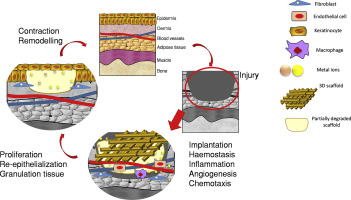

So far, they have tested some bioactive nanoparticles based on calcium on the membrane of a chicken embryo and found that blood vessels formed in it and that the cartilage ossified forming a mature bone. The tests were carried out in mice and the result was also positive. The creators of this innovative product point out that, after three years, the prosthesis would have become a bone of its own. Although it could be applied in any part of the body, it seems that the first objective would be to test it in the maxillo-facial area. Experts estimate that more than a year may pass before human trials are conducted.